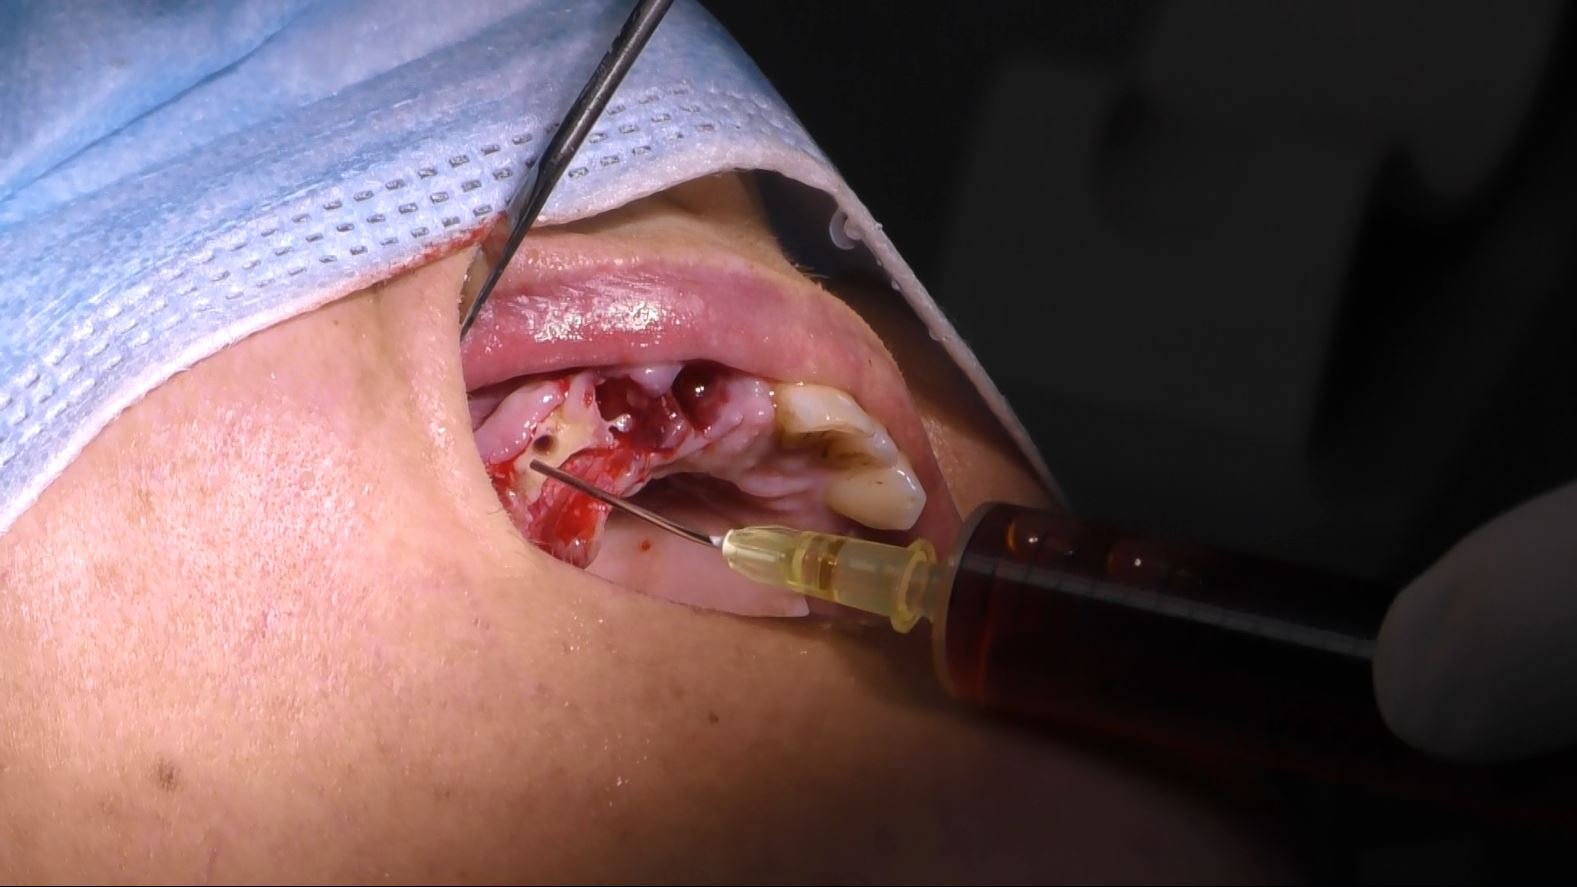

- Procedura Chirurgica Minimamente Invasiva: L’intervento è stato eseguito con un approccio minimamente invasivo, riducendo il trauma e accelerando il periodo di guarigione.

- Posizionamento degli Impianti Sottoperiostei: Gli impianti sono stati posizionati direttamente sulla superficie dell’osso mascellare, garantendo stabilità e supporto adeguati.

- Carico Immediato: Grazie all’implantologia sottoperiostea, il paziente ha beneficiato del carico immediato, ottenendo denti fissi funzionali in un tempo incredibilmente breve.